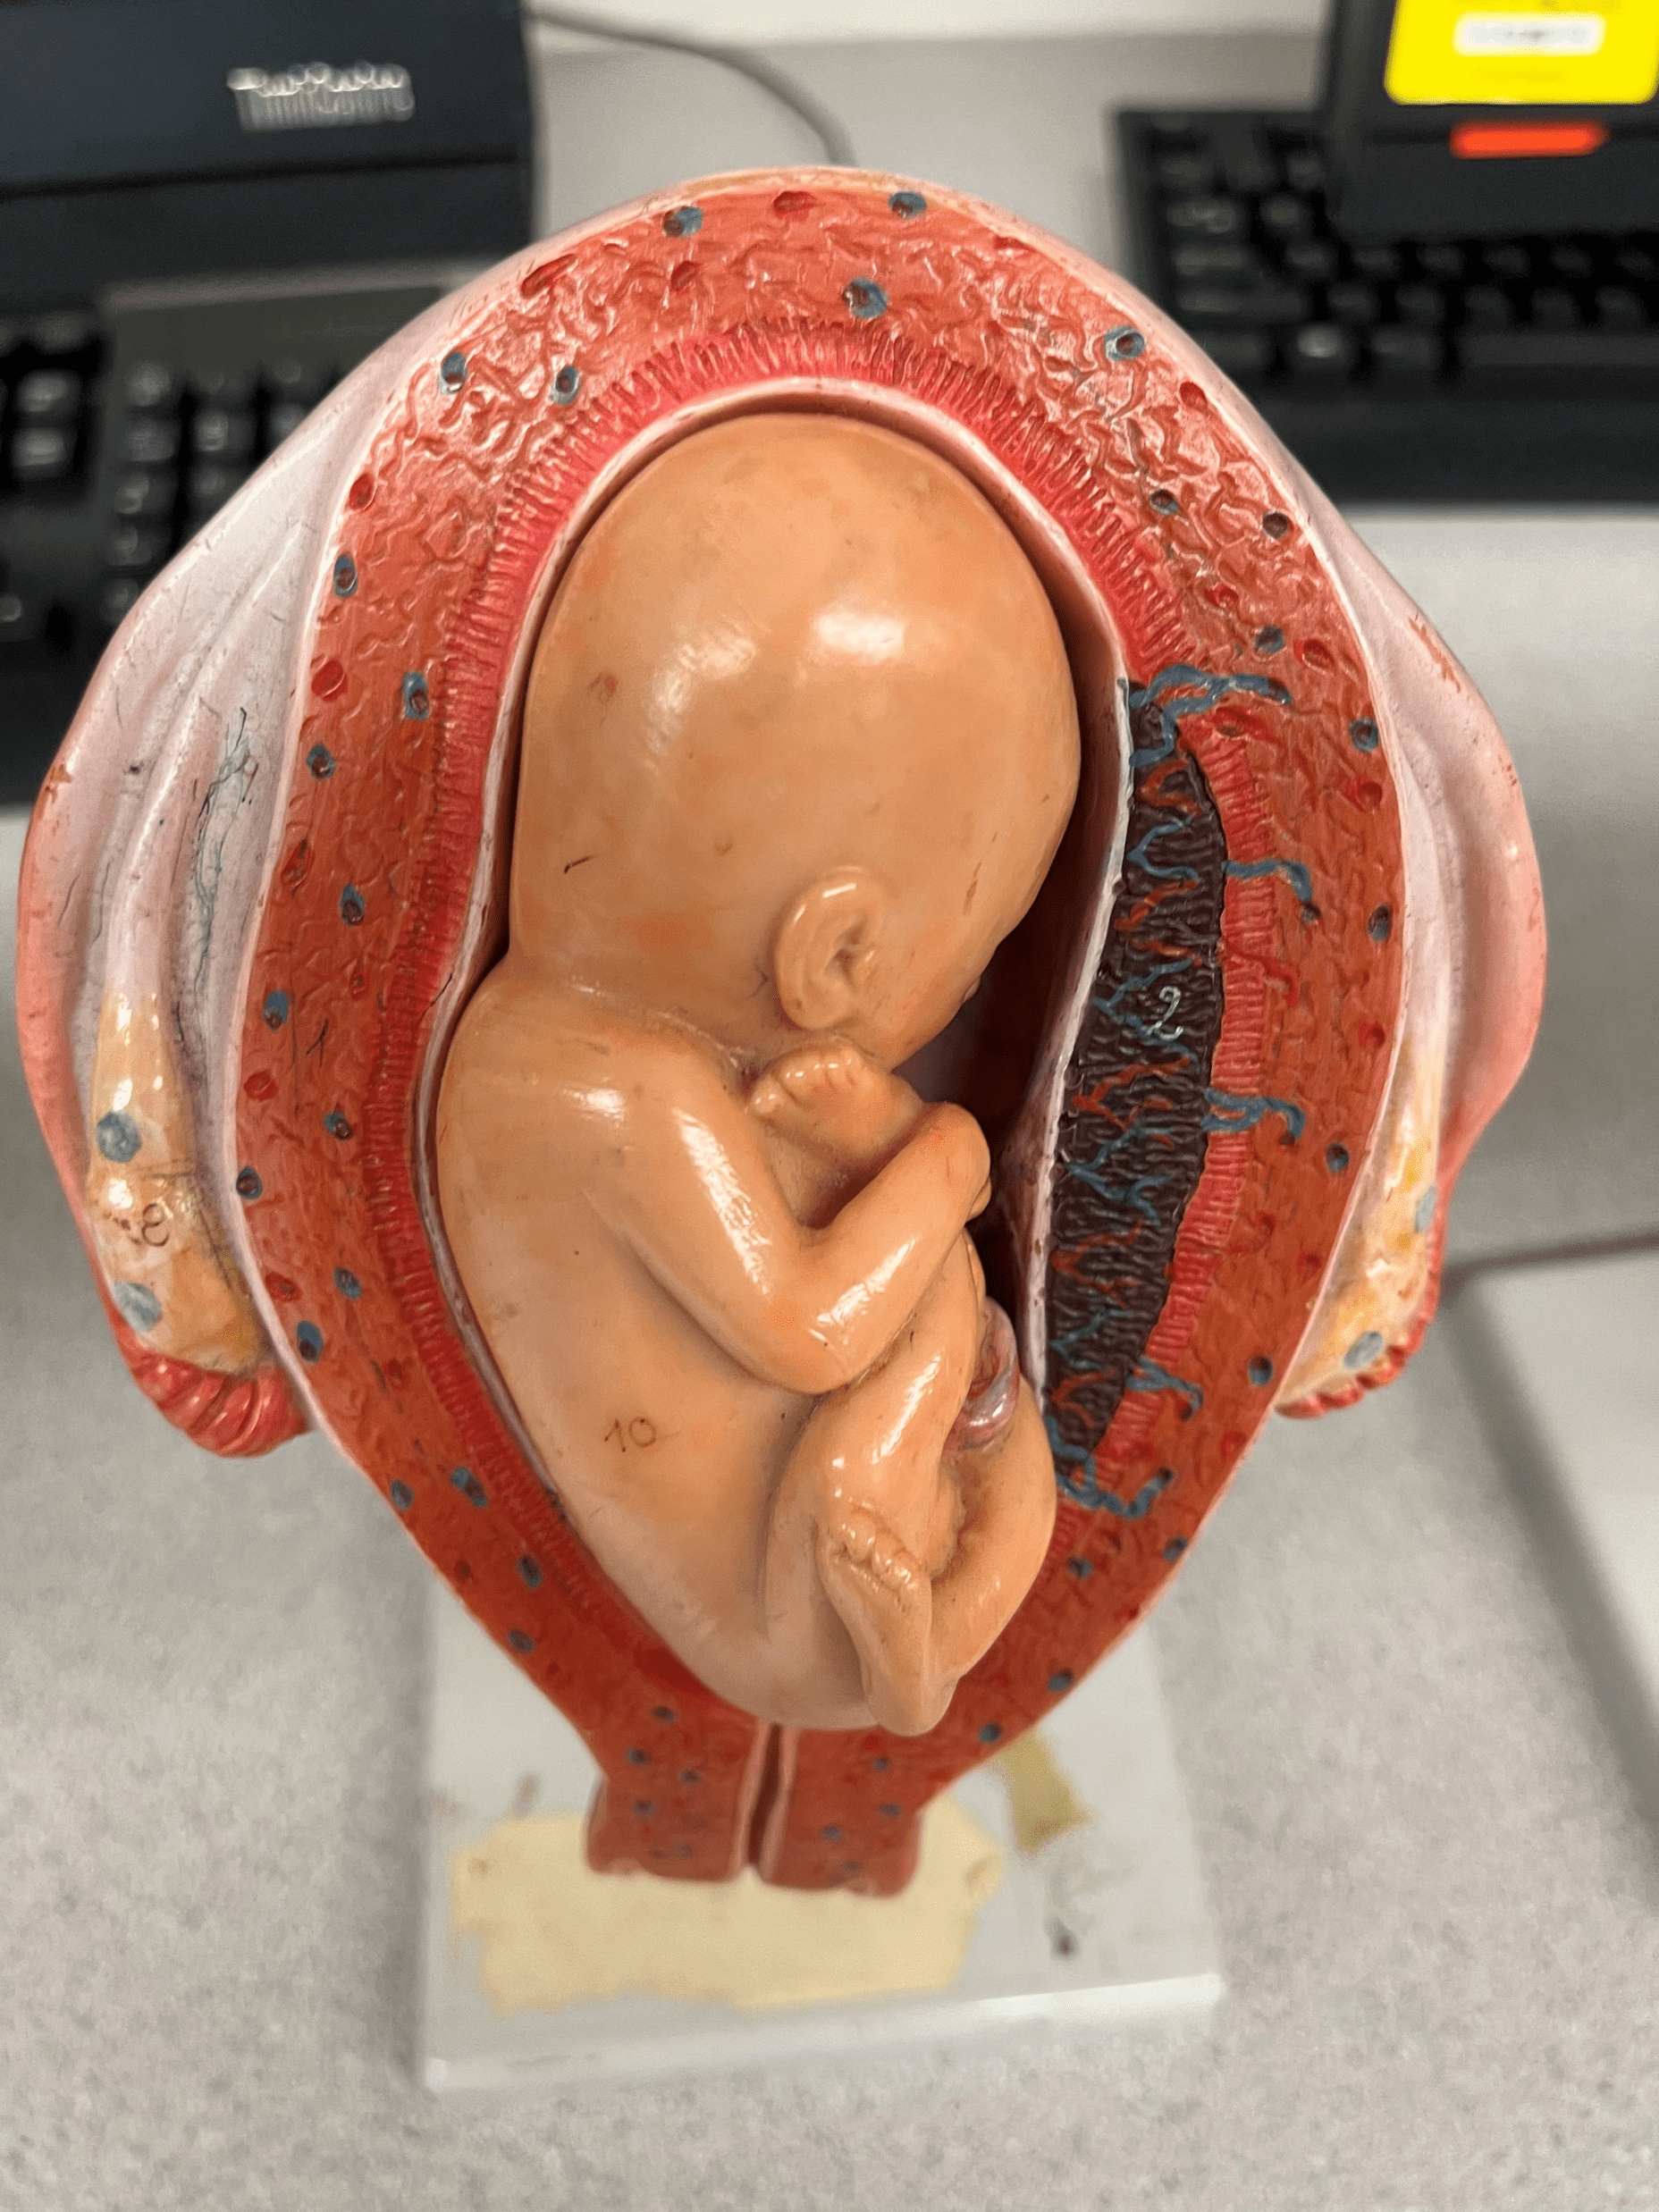

prone position

• Model of the developing fetus in the uterus.

• The position in which the fetus faces downwards.

• The position in which the fetus faces downwards.

16

New cards

breech position

• Model of the developing fetus in the uterus.

• The position in which the feet face downwards.

• The position in which the feet face downwards.

17

New cards

dorsal position

• Model of the developing fetus in the uterus.

• The position in which the fetus faces upwards.

• Also known as the supine position.

• The position in which the fetus faces upwards.

• Also known as the supine position.

18

New cards

normal position

• Model of the developing fetus in the uterus.

• The position in which the head faces downwards.

• Also known as the vertex position.

• The position in which the head faces downwards.

• Also known as the vertex position.

19